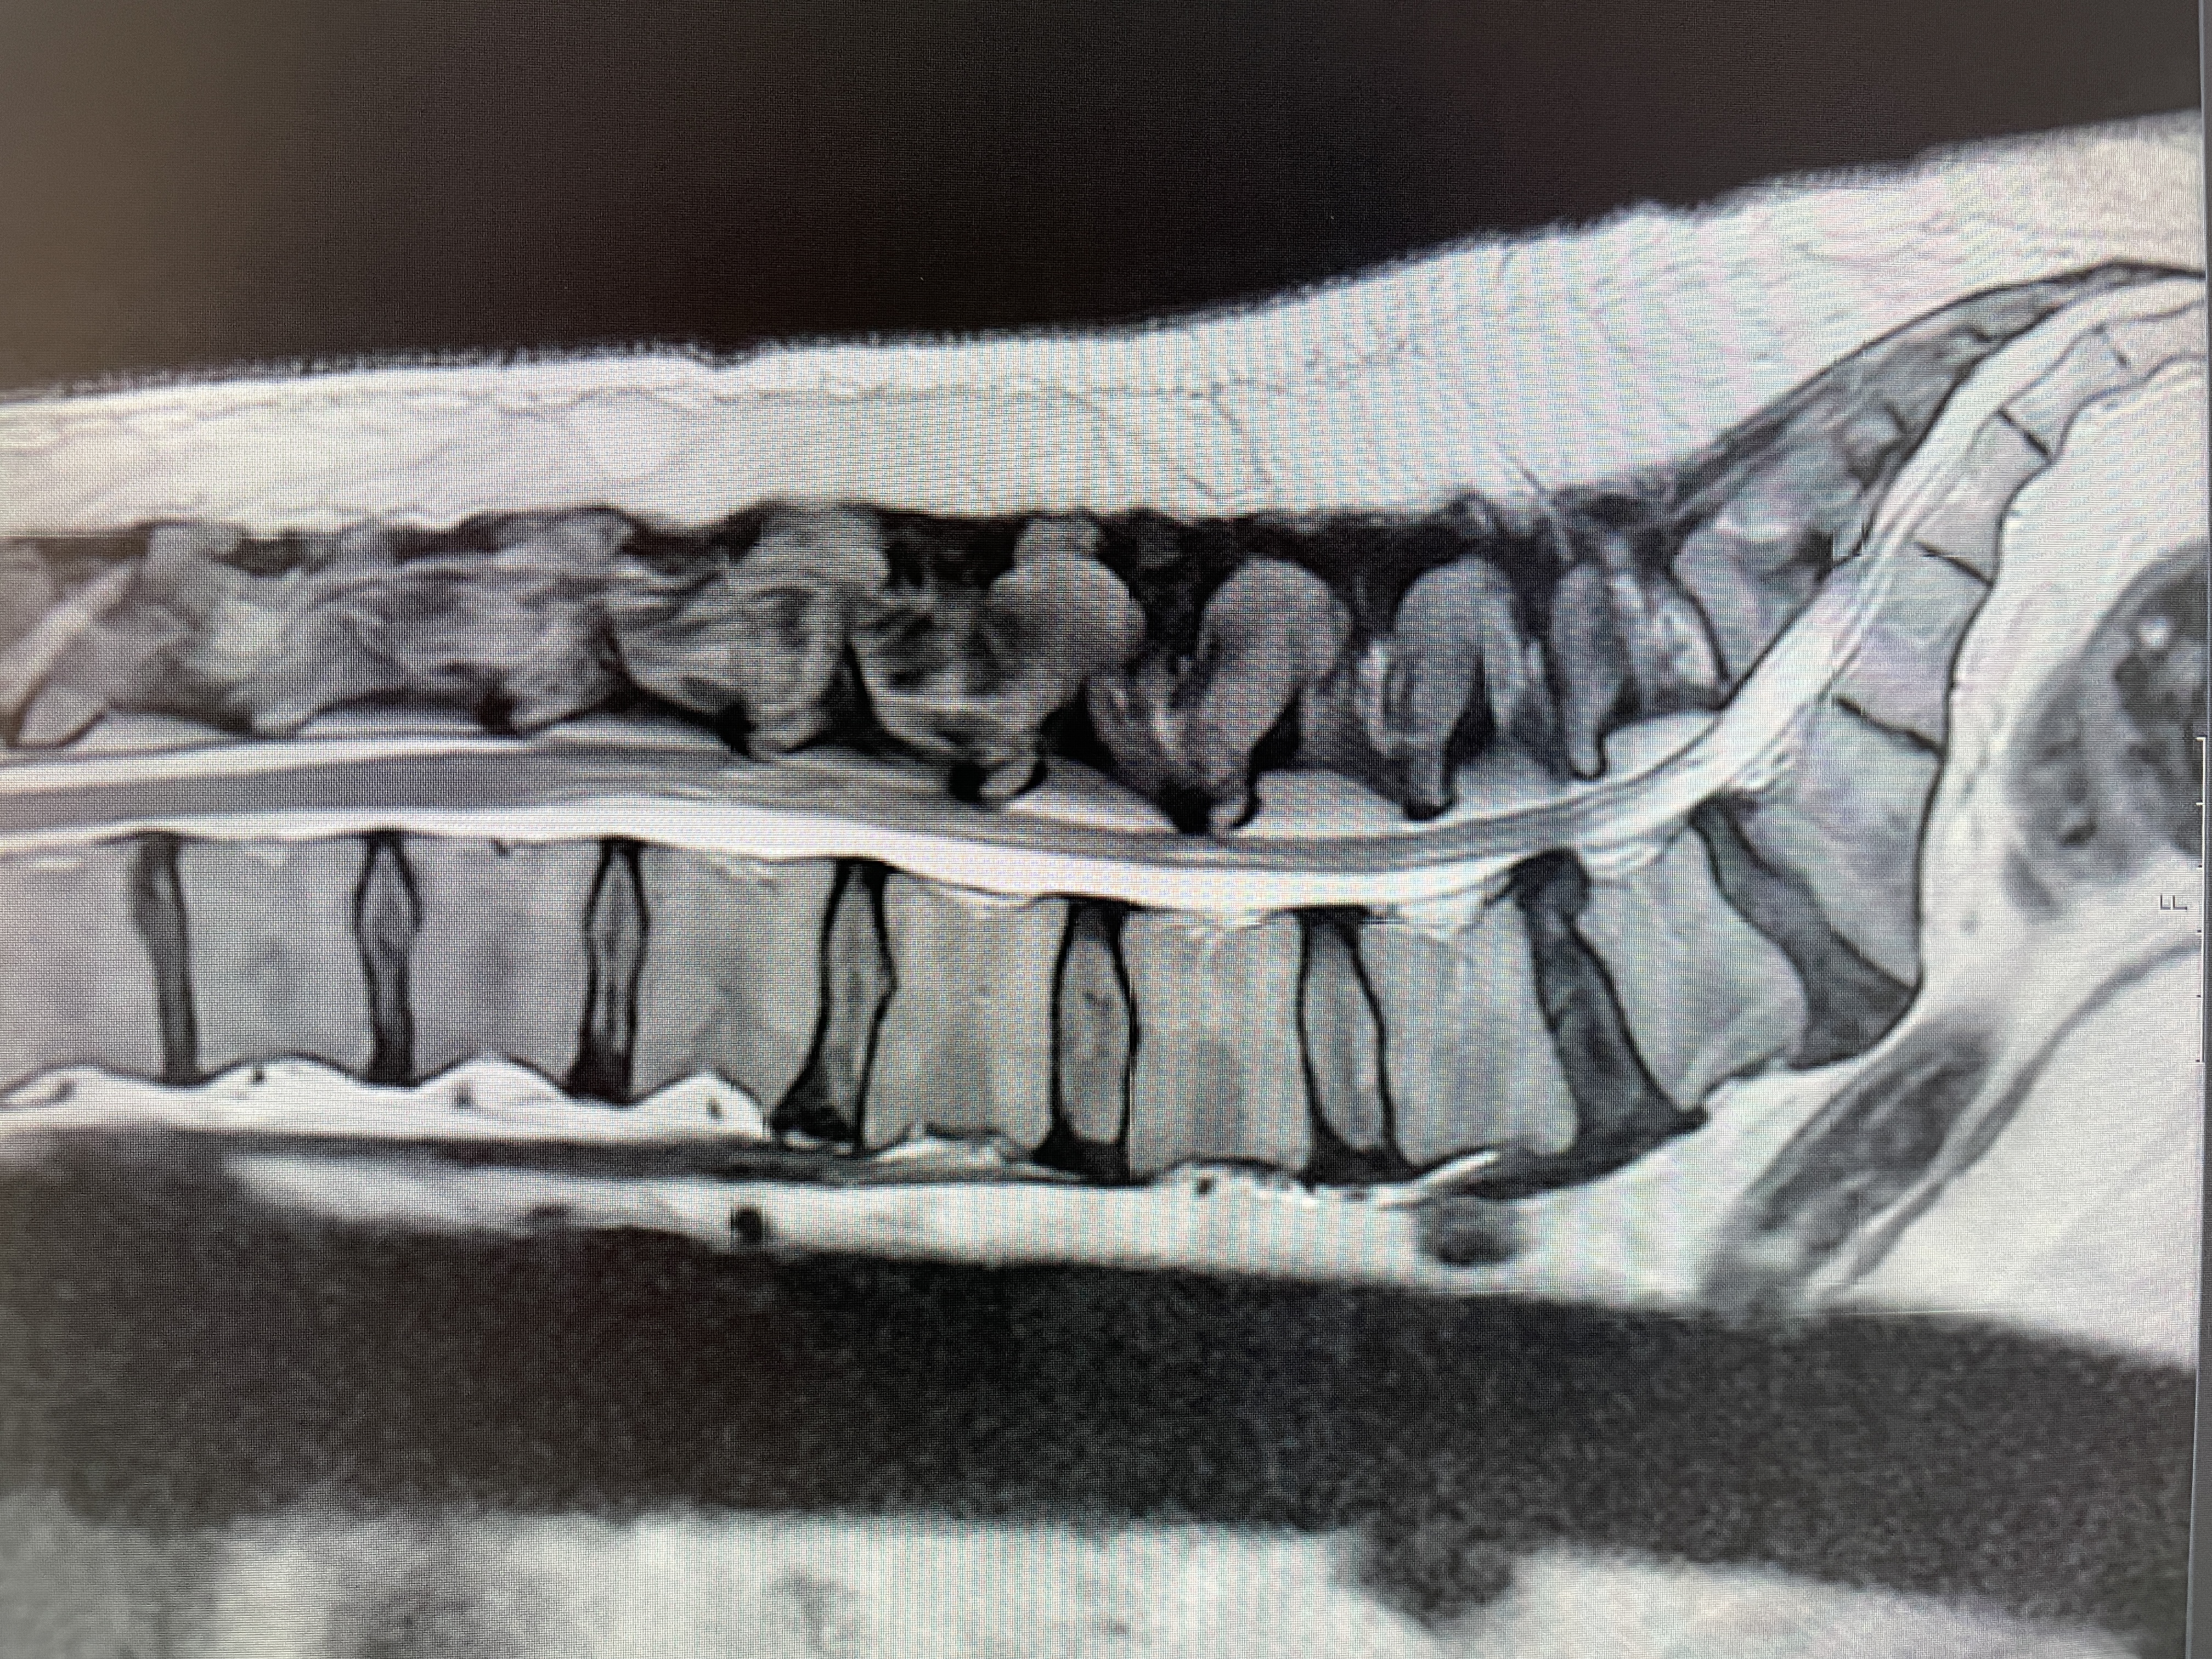

Spinalstenose er en tilstand, hvor rygradens kanal indsnævres, hvilket kan presse på nerver og forårsage smerter, følelsesløshed og svaghed i benene. Diskusprolaps opstår, når den geléfyldte pude, der fungerer som støddæmper mellem hvirvlerne, skifter ud over sin normale position og kan presse mod nerverødderne, hvilket fører til smerte, prikken eller svaghed i arme eller ben.

Diagnosen af rygsmerter herunder lænde- og nakkesmerter er ofte baseret på en kombination af symptomer, fysisk undersøgelse og billedundersøgelser som røntgen eller MR-scanning.